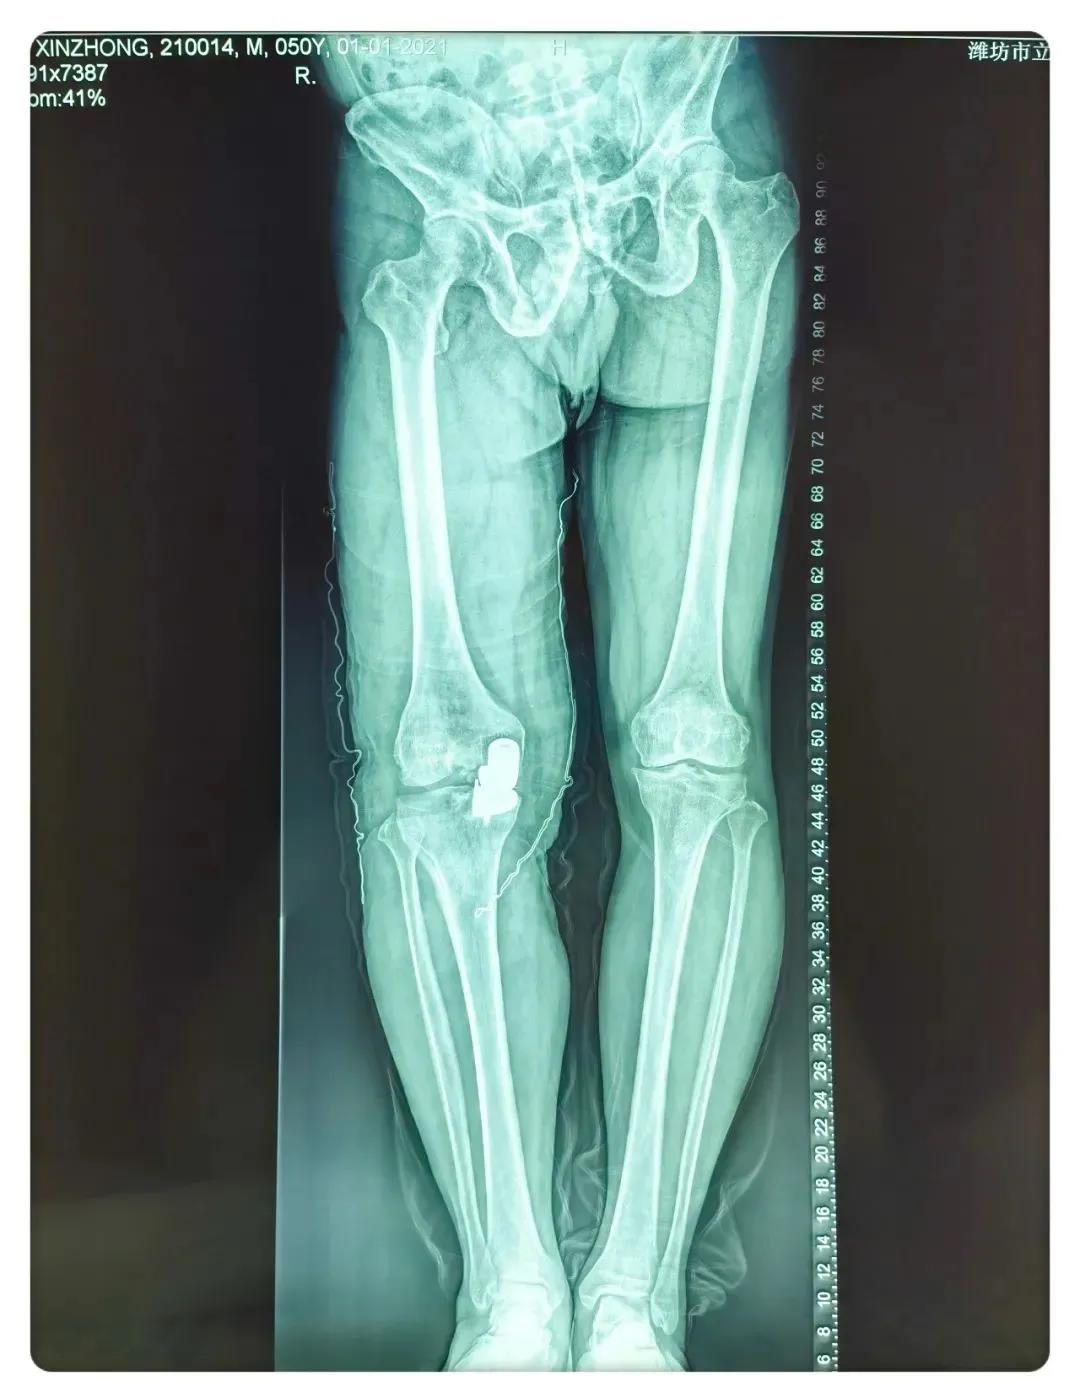

術(shù)后患者X線片